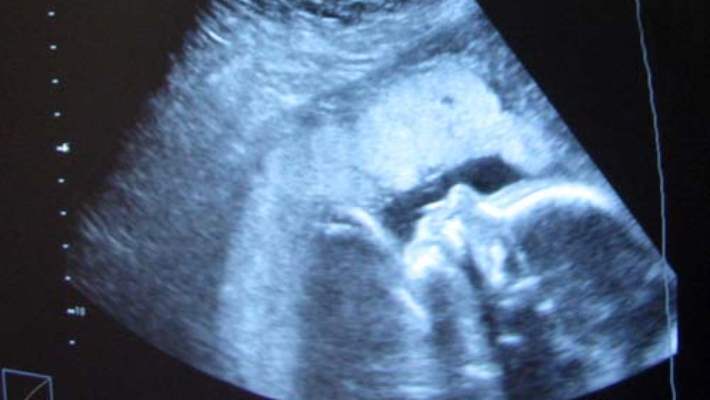

Bu etkili teknik, kadından alınan olgun yumurtaların laboratuvar ortamında erkekten alınan sperm ile döllendirilmesini ve döllenmenin ardından 3 ile 5 gün içerisinde embriyonun rahime yerleştirilmesini içerir. Tüp bebek (laboratuvar ortamından döllenme) her iki dölyatağı tüpünün de tıkanması halinde önerilir. Bu yöntem aynı zamanda endometriozis, açıklanamayan kısırlık, rahim ağzı sorunları nedeniyle oluşan kısırlık, erkeklerde kısırlık ve yumurtlama bozuklukları gibi bazı diğer sorunlara karşı da yaygın olarak kullanılır. Tüp bebek, birden fazla embriyonun rahime yerleştirilmesi halinde ikiz veya daha fazla bebek sahibi olma şansını arttırır. Tüp bebek yöntemi düzenli kan testlerini ve günlük hormon iğnelerini içerir. Kısırlık tedavisi gerçekleşmezse tüp bebek yöntemleri uygulanır.